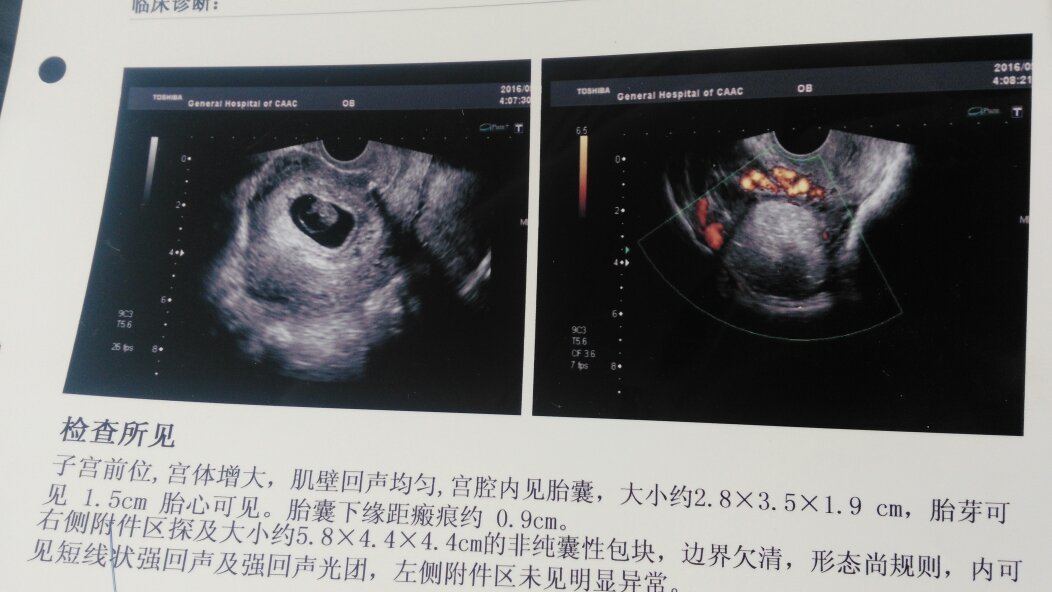

老婆至今年9月1号怀孕两个多月了,去年五月三号刨妇产生的第一胎,今天去医院检查得了畸胎瘤,该怎么治老婆至今年9月1号怀孕两个多月了,去年五月三号刨妇产生的第一胎,今天去医院检查得了畸胎瘤,请问得了畸胎瘤想要孩子对于母亲和腹中胎儿有什么危害和影响么,老婆刨妇产刀口到现在有15个月了,要是要孩子等孩子大了会不会早产或者刀口破裂,畸胎瘤要是要孩子什么时候可以做手术,怎么做。要是不要孩子现在两个多月了,又得了畸胎瘤,流产的话对女性本身和畸胎瘤有什么影响,要是能流的话什么时候做切除畸胎瘤好,下面有检查的B超图片,希望有专业大夫给个意见,不是本行专业的大夫请勿言,跪求